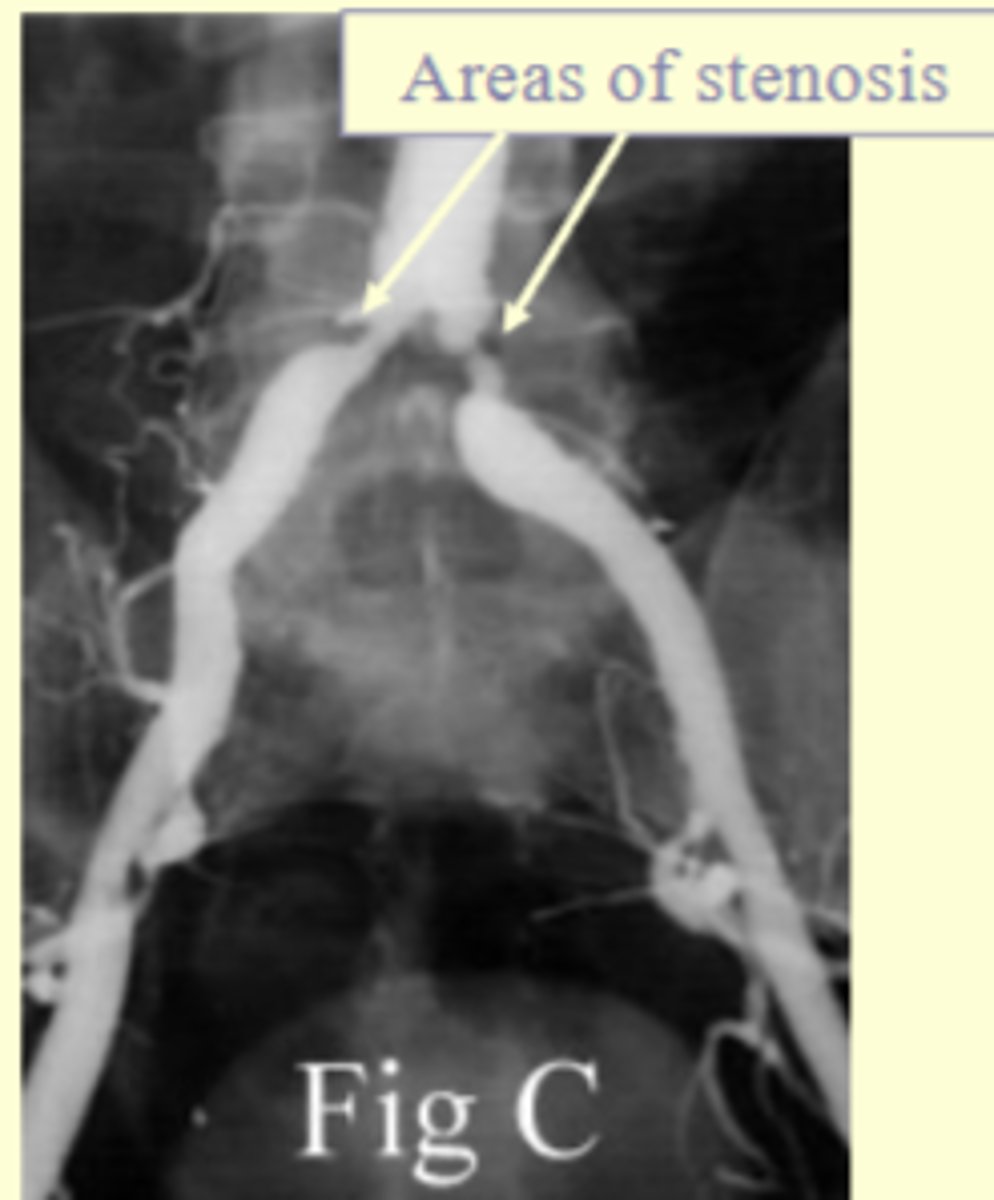

What pathologies can interventional procedures treat?

- stenosis (abnormal narrowing) of a vessel

What condition does balloon angioplasty primarily address?

Stenosis due to atherosclerosis (fatty deposits in the artery); alleviates stenosis and restores blood flow

What is Digital Subtraction Angiography (DSA)?

A technique that requires a digital system to subtract bony and soft tissue anatomy from images, leaving only contrast-filled vessels.